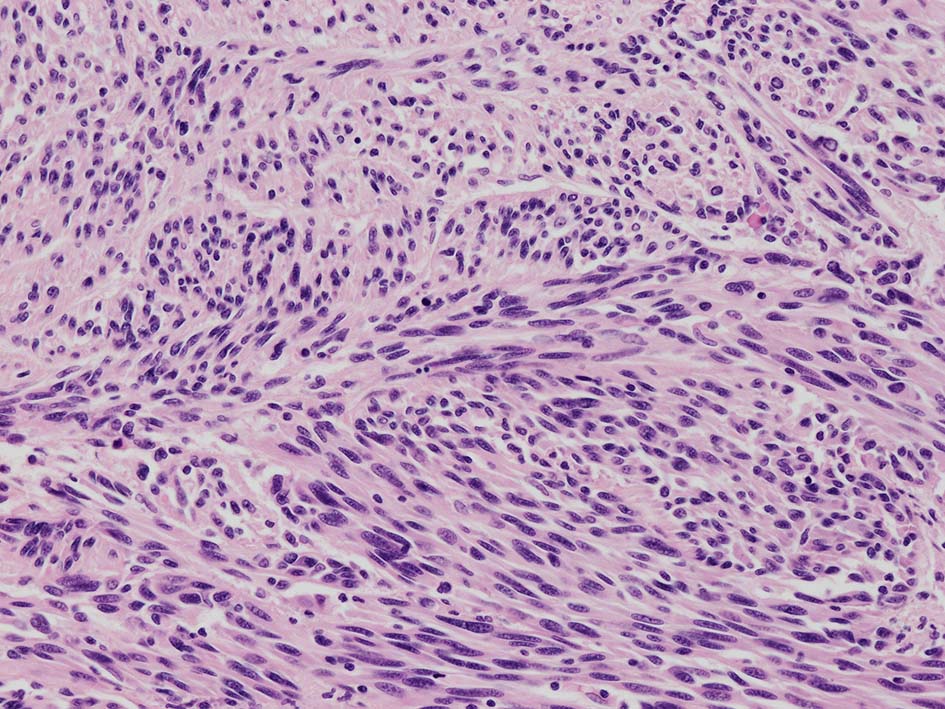

紡錘形異型メラノサイトが著明な間質反応(desmoplasia)を伴い増殖する特殊な色素性病変。*1. desmoplastic neurotropic melanomaは, desmoplastic melanomaのうち神経向性(neurotropism:神経周囲侵襲像)がめだつものでReedら*2が最初に報告した。

いずれも腫瘍細胞の異型性が乏しく, 背景の間質反応がめだつこと, メラニンの存在が目立たないことが特徴である。

病理組織所見*4